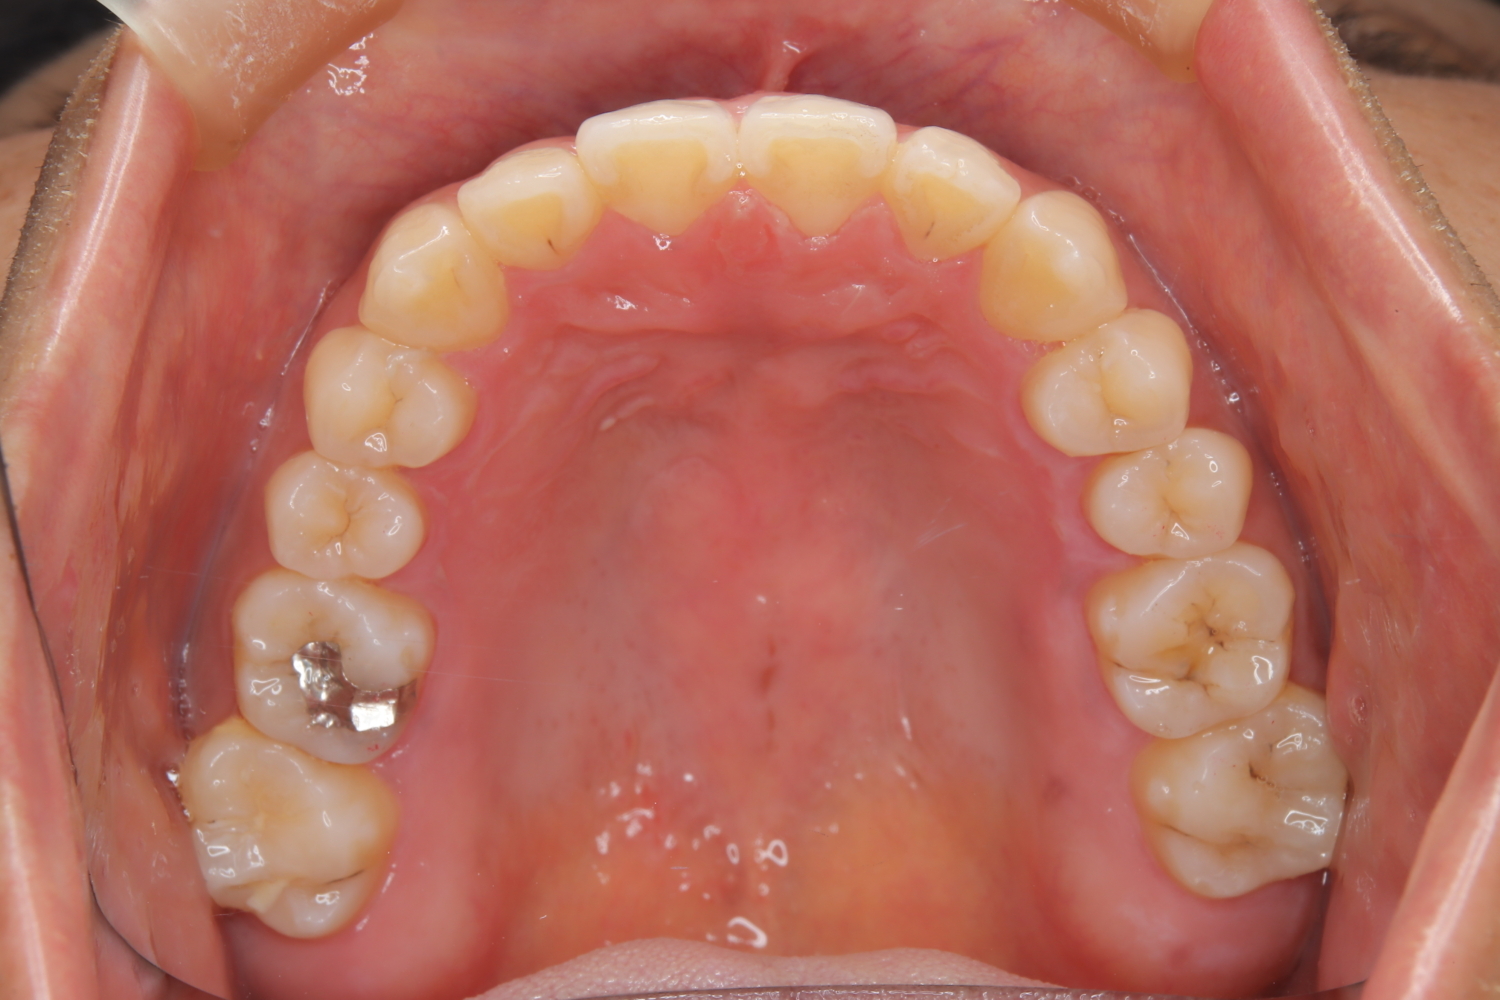

受け口の改善を主訴にご来院された患者様です。

軽度の下顎前突と診断し、マウスピース矯正装置(インビザライン)を用いて治療を行うこととしました。

治療の際はゴム掛けが必要になりましたが、患者様が非常に真面目に使用してくださったおかげで、スムーズに治療が進みました。途中の海外赴任という大きな予定変更がありましたが、そのご努力の甲斐あって、無事に渡航前に矯正を完了することができました。